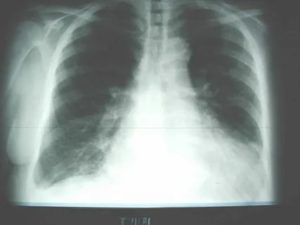

1. Рентген легких.

Позволяет установить наличие воспаления и расположения очага патологического процесса.

Для постановки диагноза необходимо сделать рентгенограмму легких, а также сдать анализы крови и (при необходимости) мокроты. Кашель на ранних стадиях проявляется не у всех.

Пневмония очень опасна. Если ее не лечить, на поздних стадиях даже антибиотики не всегда могут с ней справиться. Если есть подозрения — сделайте рентген.

Во время осмотра при аускультации легкое не прослушивается, при перкуссии отмечается притупление звука, на обзорной рентгенограмме визуализируется обширное затенение — линия Дамуазо, соответствующая уровню жидкости.

На рентгенограмме грудной клетки при пневмотораксе видна значительная область просветления, органы средостения при этом смещены в противоположную сторону.